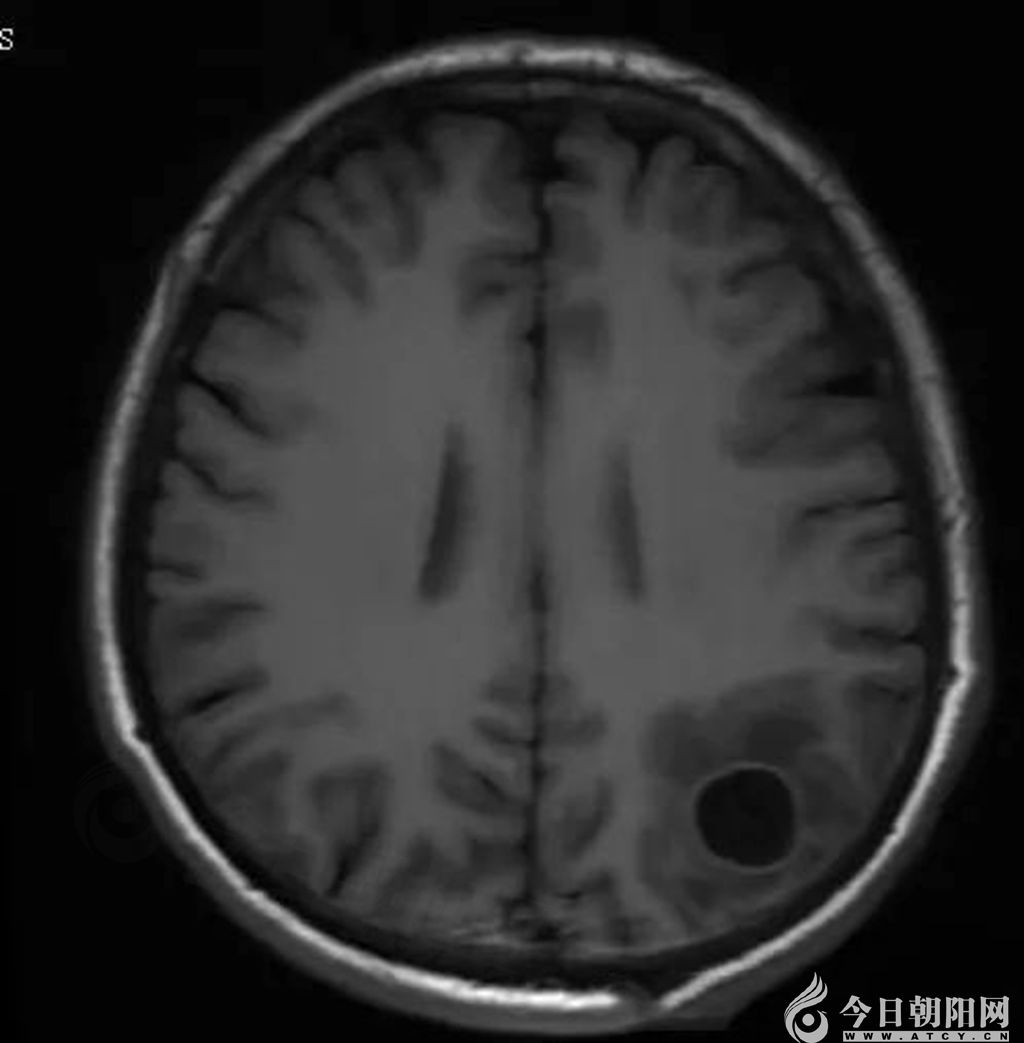

醫(yī)院介入腫瘤科副主任林麗介紹,該名患者為中年男性,因胃部經(jīng)常感到疼痛不適,來到醫(yī)院做胸部增強CT。結(jié)果顯示,患者右肺下葉結(jié)節(jié)灶,考慮肺癌可能。同時,右肺門及縱膈淋巴結(jié)轉(zhuǎn)移可能大,雙肺炎癥、肺氣腫,雙肺多發(fā)微、小結(jié)節(jié),胰管略擴張。此外,頭部MRI顯示,左側(cè)頂葉占位性病變,轉(zhuǎn)移瘤可能大。于是,患者立即到省腫瘤醫(yī)院做進一步檢查。行PET/CT顯示,右肺下葉不規(guī)則結(jié)節(jié)影,代謝增高,惡性病變不除外,患者于中國醫(yī)科大學附屬第一醫(yī)院行超聲引導下導穿刺活檢,病理診斷為惡性腫瘤。

頭部核磁